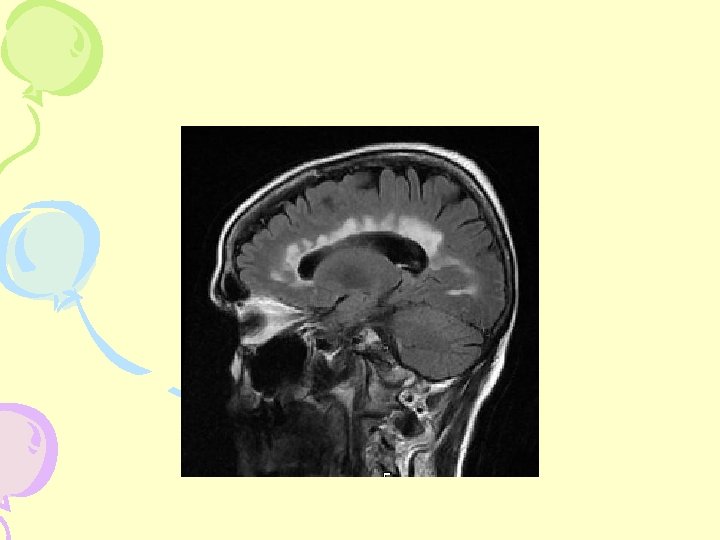

MRI- Cerebellum

MRI- Spine